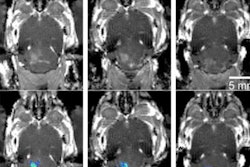

Diffusion tractography uses the movement of water molecules to identify tracts that connect different parts of the brain. It can be used to pinpoint the part of the thalamus to treat with focused ultrasound. Image courtesy of the University of Texas Southwestern Medical Center.

Diffusion tractography uses the movement of water molecules to identify tracts that connect different parts of the brain. It can be used to pinpoint the part of the thalamus to treat with focused ultrasound. Image courtesy of the University of Texas Southwestern Medical Center.These techniques show promise in identifying diseased tissue caused by Parkinson's or essential tremor, the group wrote. In fact, Shah and colleagues plan to participate in a multicenter clinical trial with collaborators at the Mayo Clinic in Rochester, MN, testing the diffusion tractography method in patients, according to the university statement.